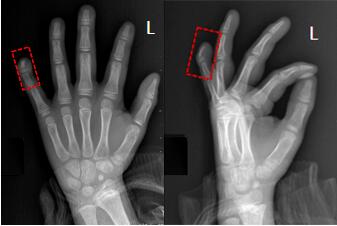

常見的單純性畸形,通常根據(jù)畸形的特點(diǎn)來命名。比如多指稱為多指,兩個或兩個以上的手指相連而不能分開稱為并指,手指長得過大而粗大稱為巨指。

3.多指:橈側(cè)多指(復(fù)雜拇指畸形);尺骨側(cè)多指(小指多指);中指;(4)復(fù)雜性(以上兩者之一同時存在)。